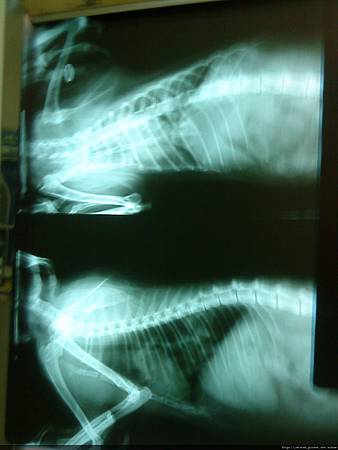

然後,2009年底開始會喘,我們從新竹看到台北

一開始的肺還不算太花阿~~

到最後的X光片可以當做我解說貓咪心輪在那兒的教材了